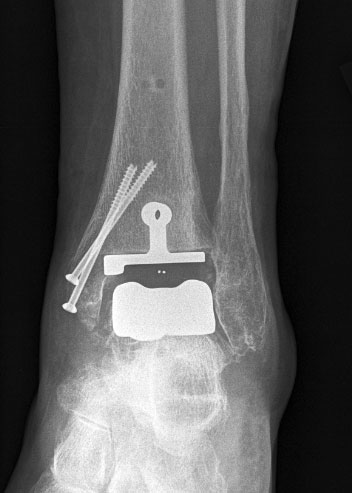

• Prothesenplanung anhand von Röntgenschablonen (Abb. 1 und 2).

Osteosynthese eines intraoperativ frakturierten medialen Malleolus mit perkutanen Schrauben.

Abbildung 19

Mögliche Ursachen können eine zu weit medial plazierte Tibiakomponente oder eine zu weit mediale, nicht nach lateral konvergierende Sägerichtung im Rahmen der ventrodorsalen distalen Tibiaresektion sein (Abb. 19).